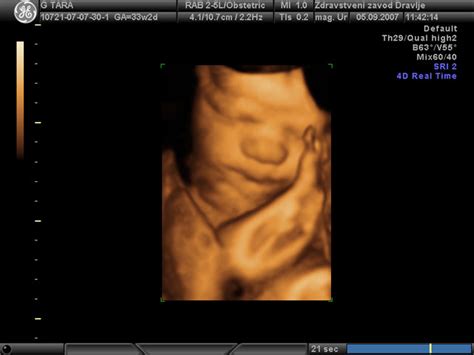

- Velikost ploda: Če je plod nadpovprečno velik (makrozomija), kar je lahko ocenjeno z ultrazvokom, lahko predstavlja izziv za vaginalni porod. V takšnih primerih, ko otrok presega določeno težo, se lahko odločitev za carski rez sprejme, da se preprečijo morebitni zapleti med porodom, kot je težko iztiskanje otroka ali poškodbe medeničnega obroča.